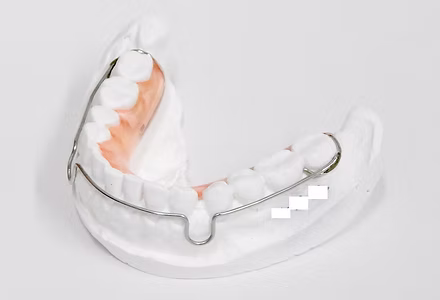

小児矯正